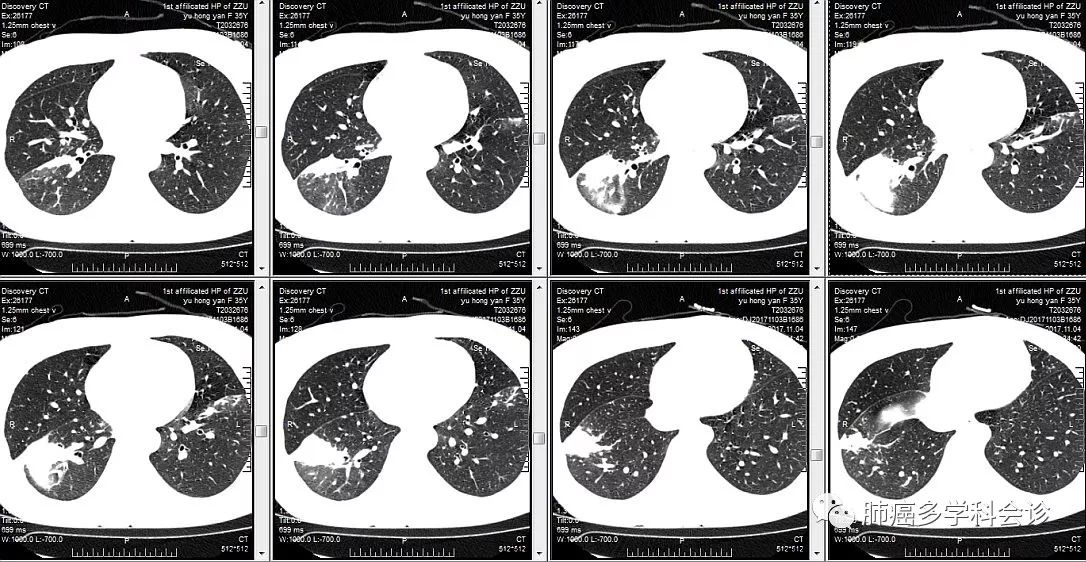

患者余HY,女,35岁。间断胸痛3月余,咳嗽咳白色粘痰,低热。当地CT:双肺下叶炎症,右下肺斑片状密度影较前扩大。支气管镜未见明显异常。

入院后胸部CT如下: